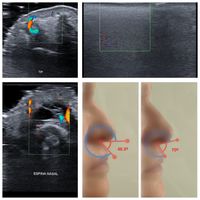

Rinomodelación asistida por ecografía

¿En qué consiste el curso? Aprender a realizar rinomodelación infiltrativa, planificando con seguridad el tratamiento mediante ecografía estética. Identificar las mejores opciones y vías de acceso para cada objetivo; y los pacientes en los que no se pueda realizar por alguna razón, evitando que sufran una complicación.

¿Qué obtengo de este curso? Es un entrenamiento one-to-one o en grupos de hasta 2 alumnos, 80% práctica tutorizada de los alumnos, en el que aprender o perfeccionar tus habilidades en planificar y realizar rinomodelación con el apoyo de la ecografía, convirtiéndola en un tratamiento mucho más seguro y controlado, con menor probabilidad de complicaciones (hematomas, inflamación, nódulos, complicaciones vasculares...)

¿Cómo se desarrolla el curso? Es un curso de unas 7h de duración, mañana y tarde. Se realiza en una clínica U.48, la del alumno o la del profesor. Hacemos un breve repaso teórico a las técnicas, materiales y vías de acceso en rinomodelación, y tras ello el alumno realiza el diagnóstico y tratamiento de dos pacientes (aportados por el alumno), uno por la mañana y otro por la tarde, tutorizado en todo momento por el Dr. Ferrandis.